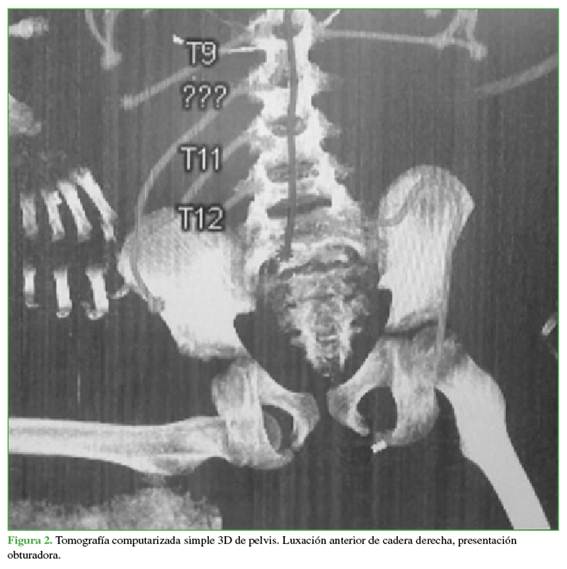

Se realizó una intubación orotraqueal. La TC de cráneo mostró un hematoma epidural y una fractura frontotemporal sin criterios quirúrgicos. En primera instancia, la TC de pelvis reveló una incongruencia articular coxofemoral derecha, caracterizada por una luxación anterior en presentación obturadora (Figura 2), se descartaron lesiones asociadas.

En este caso, el niño sufrió una luxación anterior, la menos frecuente, ya que el 95% de las luxaciones son posteriores.12 Baumann y cols. comunicaron una prevalencia del 2,8% para las luxaciones anteriores con compromiso del foramen obturador.11

La TC fue útil para confirmar la dirección de la luxación, aunque no es ideal para detectar fracturas acetabulares en niños debido al cartílago no osificado; la RM sería más adecuada,8 pero no se realizó. El caso correspondió a una luxación aislada (grado I),10 sin lesiones asociadas, lo cual es habitual en niños menores de 8 años, en quienes es poco frecuente encontrar fracturas acetabulares.14 Las lesiones condrales y óseas aumentan con la edad.3